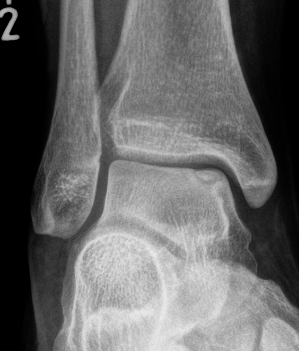

Xray

Stage II medial osteochondral fragments

Stage III medial osteochondral fragments

Stage IV anterolateral osteochondral fragment